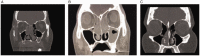

Results: A total of 356 patients had scans available for review; 80 (23%) patients were categorized into the AFRS group, 101 (28%) in the AERD group, 43 (12%) in the CCAD group, and 132 (37%) in the CRSwNP NOS group. Septal inflammatory involvement and oblique middle turbinate orientation on CT scans was higher in both AERD patients and CCAD patients as compared to AFRS and CRSwNP NOS patients (P < .05). Olfactory cleft opacification was increased in the AERD group compared to all other diagnoses (P < .05). The CCAD group showed lower LM scores compared to all other groups (P < .05), and the AFRS group revealed the greatest differences between left and right LM grades, representing unilaterality of disease (P < .05).